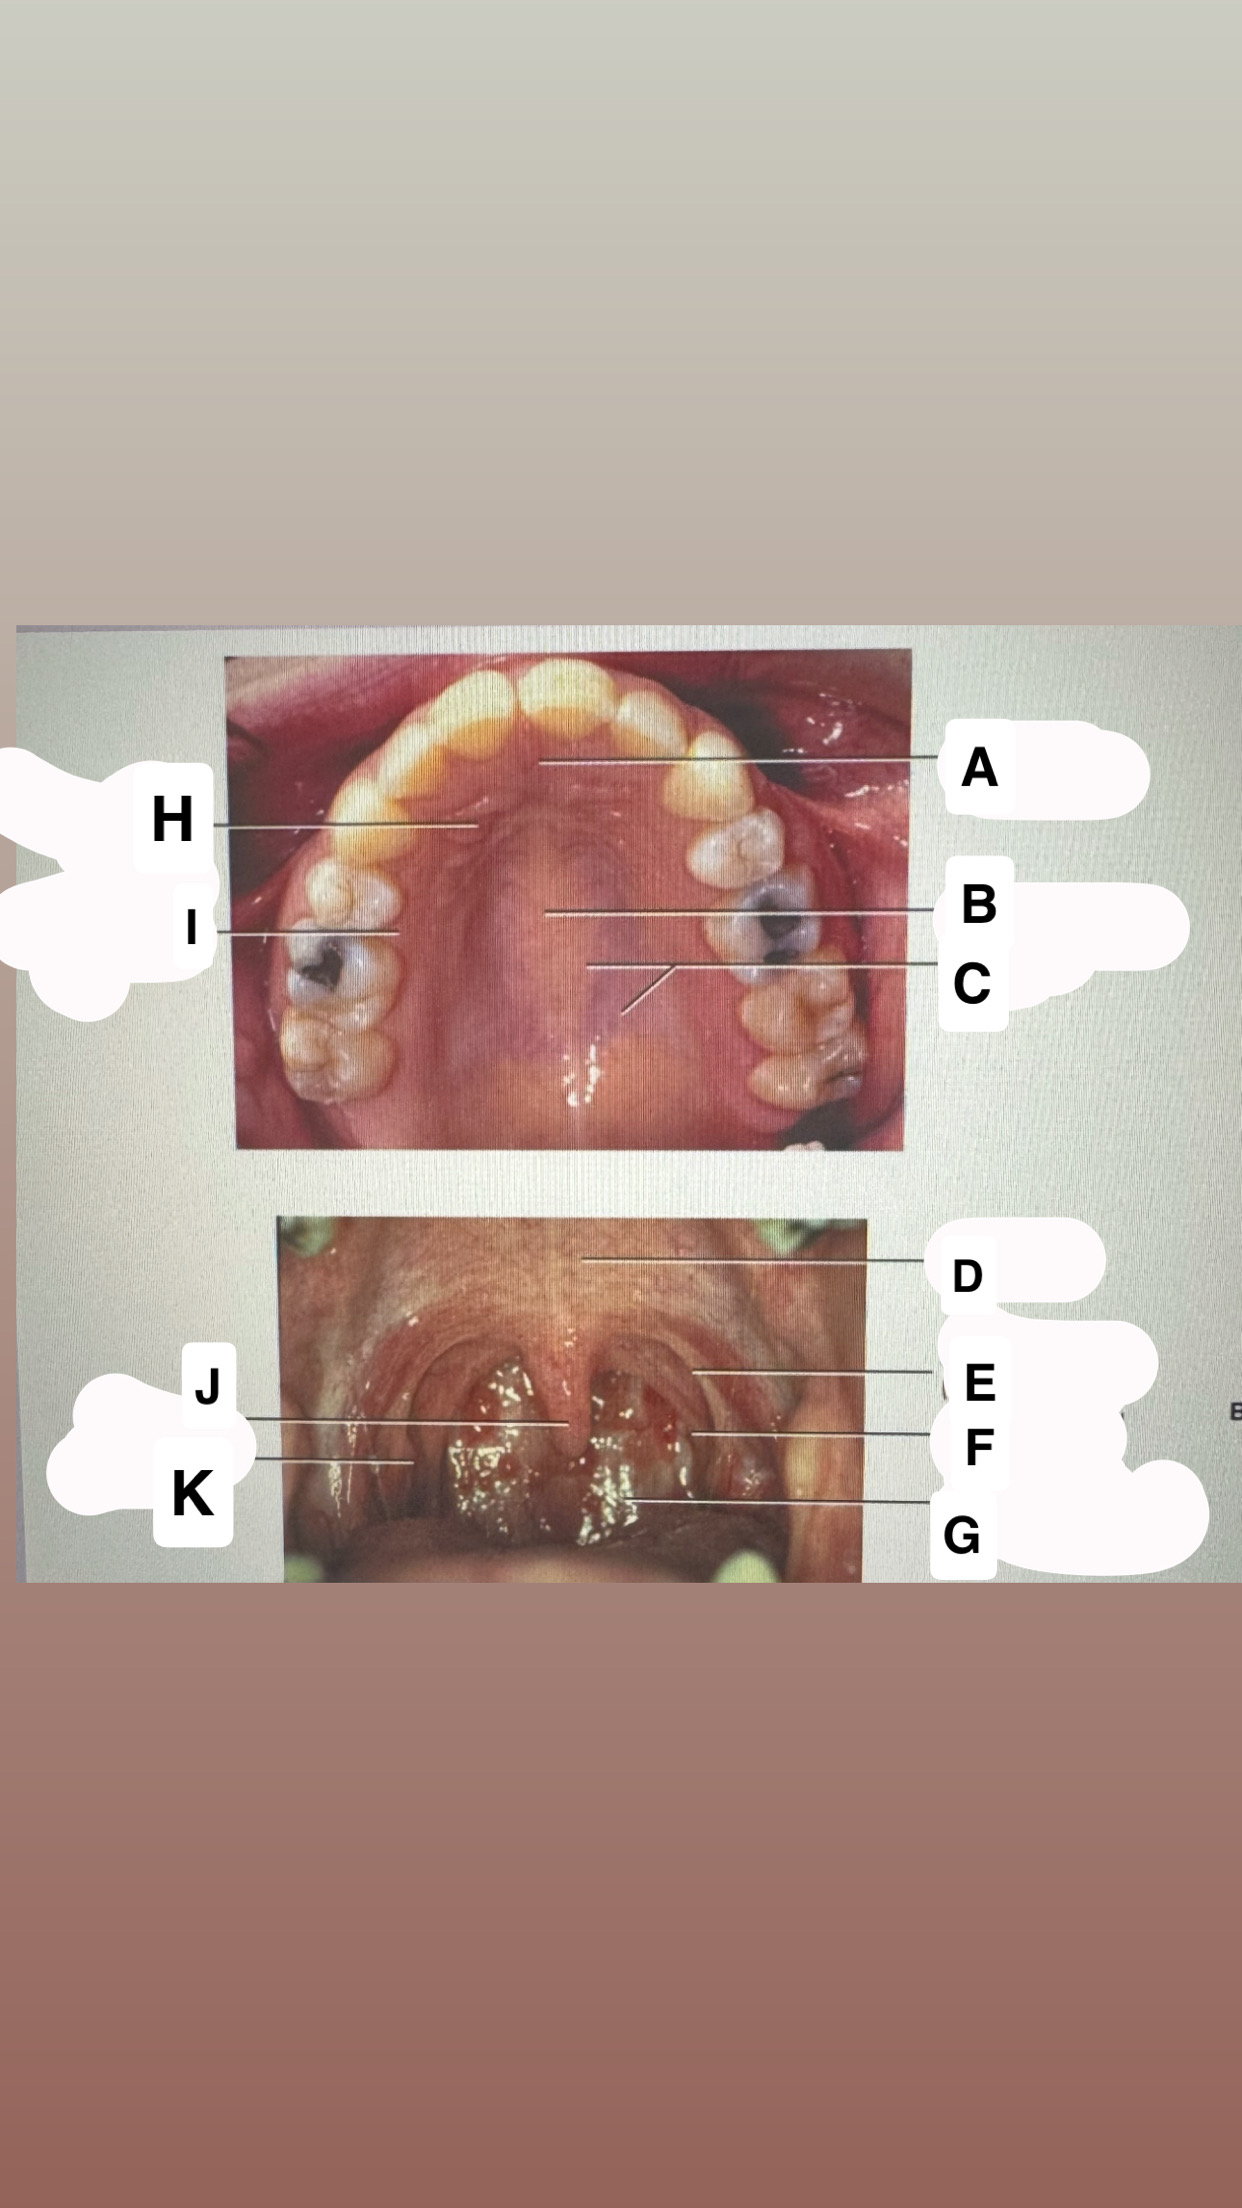

<p>Identify A</p>

- Incisive papilla

<p>Identify C</p>

• Palatal glands

<p>Identify D</p>

Soft palate

<p>Identify H</p>

Palatal rugae

<p>Identify I</p>

Lingual (palatal)

gingiva

<p>Identify J</p>

Uvula

<p>Identify K</p>

Palatine tonsil